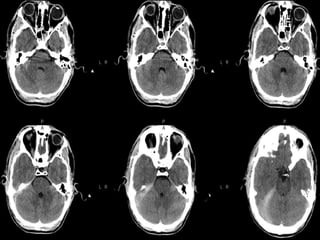

Subarachnoid hemorrageSubarachnoid hemorrage Canoriginate from direct vessel injury, contused cortex or intraventricular hemorrhage. Look in the interpeduncular cistern and Sylvian fissure Usually focal (but diffuse from aneurysm) Can lead to communicating hydrocephalus

Intraventricular hemorrhageIntraventricular hemorrhage Mostcommonly due to rupture of subependymal vessels Can occur from reflux of SAH or contiguous extension of an intracerebral hemorrhage Look for blood-cerebrospinal fluid level in occipital horns